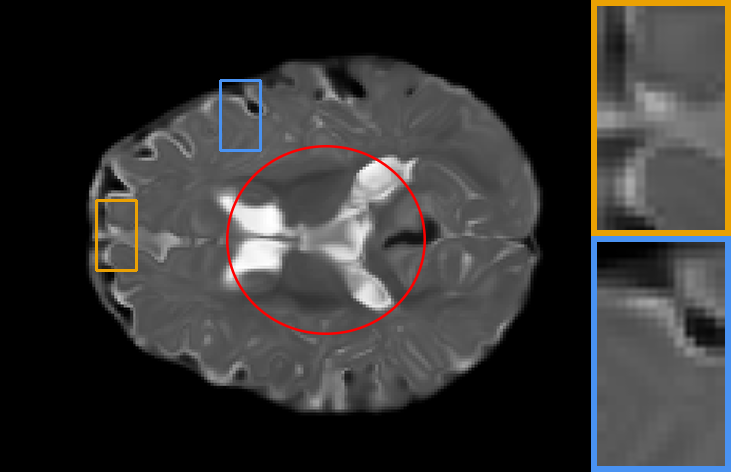

| Brain T1-to-T1 | Brain T2-to-T2 | Knee T1-to-T1 | Brain T2-to-T1 |

IV-C2 Automatic learning across registration tasks

To explore the influence of model weights, architectures, and training objectives in registration performance and verify the benefit from adaptive feature extraction cell, task-aware deformation estimation cell design, and scenario-oriented training objectives, we made groups of contrast experiments, covering diverse registration scenarios. Specifically, we first train a registration model on PPMI brain T1 MR image-to-atlas registration tasks, then take the model as initialization to adopt our auto-search strategy to register images of other different scenarios. The scenarios cover registration on another ADNI dataset, Brain T1-to-T1, Brain T2-to-T2, Knee T1-to-T1 and Brain T2-to-T1 setups.

In Table. II, we directly apply the model (with , , and ) on the PPMI dataset to other scenarios, corresponding to the 1st column result, showing poor performance. Whereas performances of re-trained models (with task-specific model weight ) on these tasks correspond to the 2nd column. We also demonstrate the performance of searched networks with auto-learned feature cells , deformation cells , and training objectives , corresponding to the 3rd to 5th columns. To fully capture the benefit of the proposed technique, we further report the increase in registration accuracy for cases where all hyperparameters are searched in the last column. We can observe that, firstly, retraining the model for different alignment tasks will result in better performance. Secondly, searched tailored architecture and training objectives largely improve numerical results, which means automatic learning combining training objectives, architectures and hyperparameters can achieves excellent alignment performance in different alignment scenarios.

Also, the models on the diagonal with a blue background perform second best which can be seen from Table. II, providing meaningful indications and conclusions. Firstly, when transferring to another dataset or image contrast, feature extraction plays a dominant role in model performance. Secondly, whereas transferring to another anatomical structure such as the knee data, regulating the deformation estimation section has a more significant impact on the performance of the model. Lastly, adjusting the training objective plays a more important role in the performance of a registration network when transferring to multi-modal datasets.